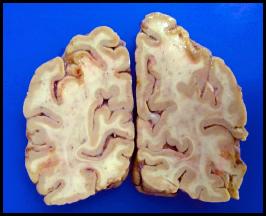

Hypoperfusion

Here are the corresponding coronal sections through the brain. Do these fit with your observations on the CT scans?